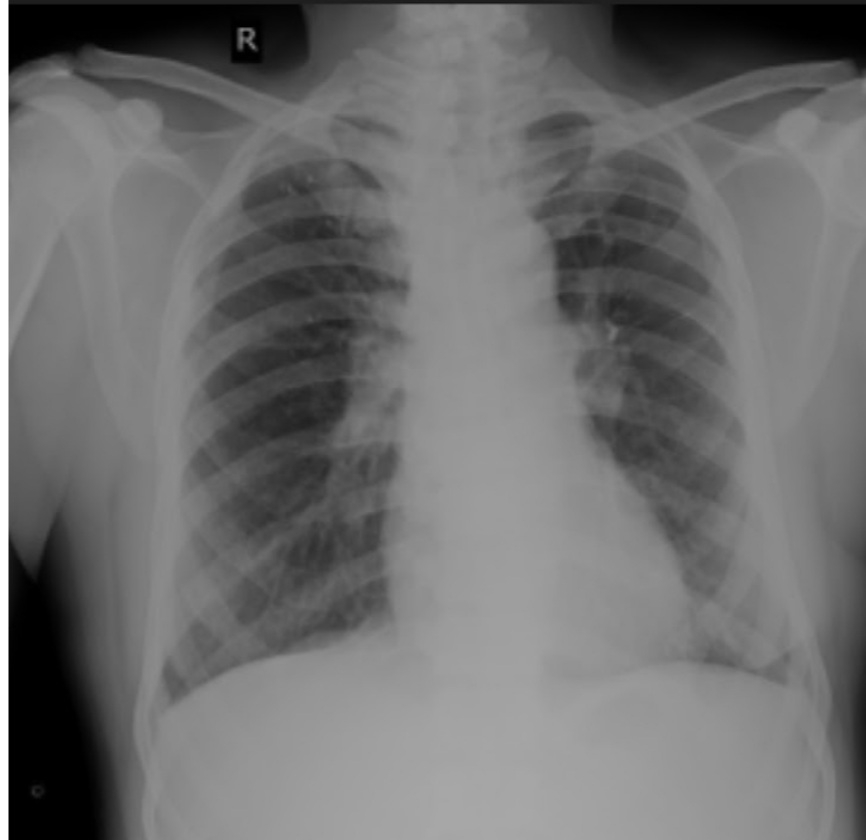

RS: BAE+, NVBS,no added sounds